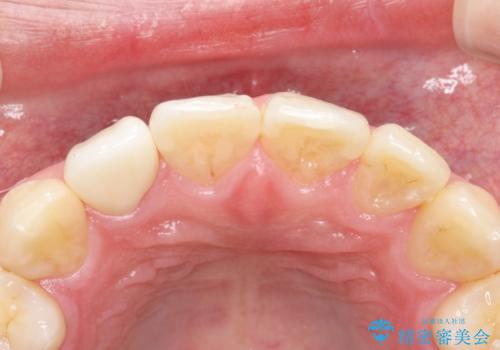

根管治療を含め、オールセラミッククラウンにて修復治療を行っております。

当院の根管治療は100%ラバーダムを使い無菌的な処置に配慮して行っております。

今回は歯冠修復にe-maxプレスクラウンを使っています。